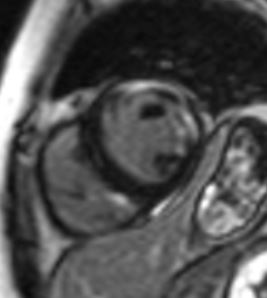

Case Presentation: A 32-year old woman with past medical history significant for myasthenia gravis (MG), polymyositis, and systemic lupus erythematosus (SLE) was admitted to the hospital for evaluation of non-sustained ventricular tachycardia (NSVT) discovered during 72-hour Holter monitoring. Patient had been experiencing palpitations with heart rate up to 200 beats per minute recorded on her smart watch, associated with substernal chest pressure and exertional dyspnea, for one month. Her medications included pyridostigmine, mycophenolate mofetil and prednisone; she was also receiving monthly plasmapheresis due to severe exacerbation of myasthenia symptoms 4 months prior. Labs on presentation were significant for troponin elevation at 10.6 ng/mL (normal: <0.04), BNP 462, hypogammaglobulinemia, hypocomplementemia, and normal ESR and CRP. CT Angiogram of the coronaries was negative for atherosclerosis. Hypokinesis of the inferior myocardial wall was noted on echocardiogram. Cardiac MRI showed reduced left and right ventricular systolic function, with a left ventricular ejection fraction (LVEF) of 41%. Multiple biventricular areas of myocardial enhancement were present, indicating an acute injury. Infectious workup, including a full viral panel, was negative. Review of skeletal muscle biopsy performed at an outside hospital showed giant cells, inconsistent with a diagnosis of polymyositis. Patient had previously 2 positive and 1 negative dsDNA antibody tests; repeat anti-dsDNA using a crithidia assay, which has the highest specificity for SLE, was negative. Hypocomplementemia and hypogammaglobulinemia were attributed to recent plasmapheresis. Further workup showed positive acetylcholine receptor binding, blocking, and modulating antibodies, as well as positive anti-titin and anti-striational muscle antibodies, all seen in MG. No thymoma was present on Chest CT. Treatment with intravenous high dose steroids and mycophenolate was initiated with resolution of ventricular arrhythmias. Plasmapheresis was switched to weekly intravenous immunoglobulin (IVIG) administration. Amiodarone was started for arrhythmia control. Follow-up echocardiogram 7 days after treatment initiation showed improved LVEF of 45-49%.